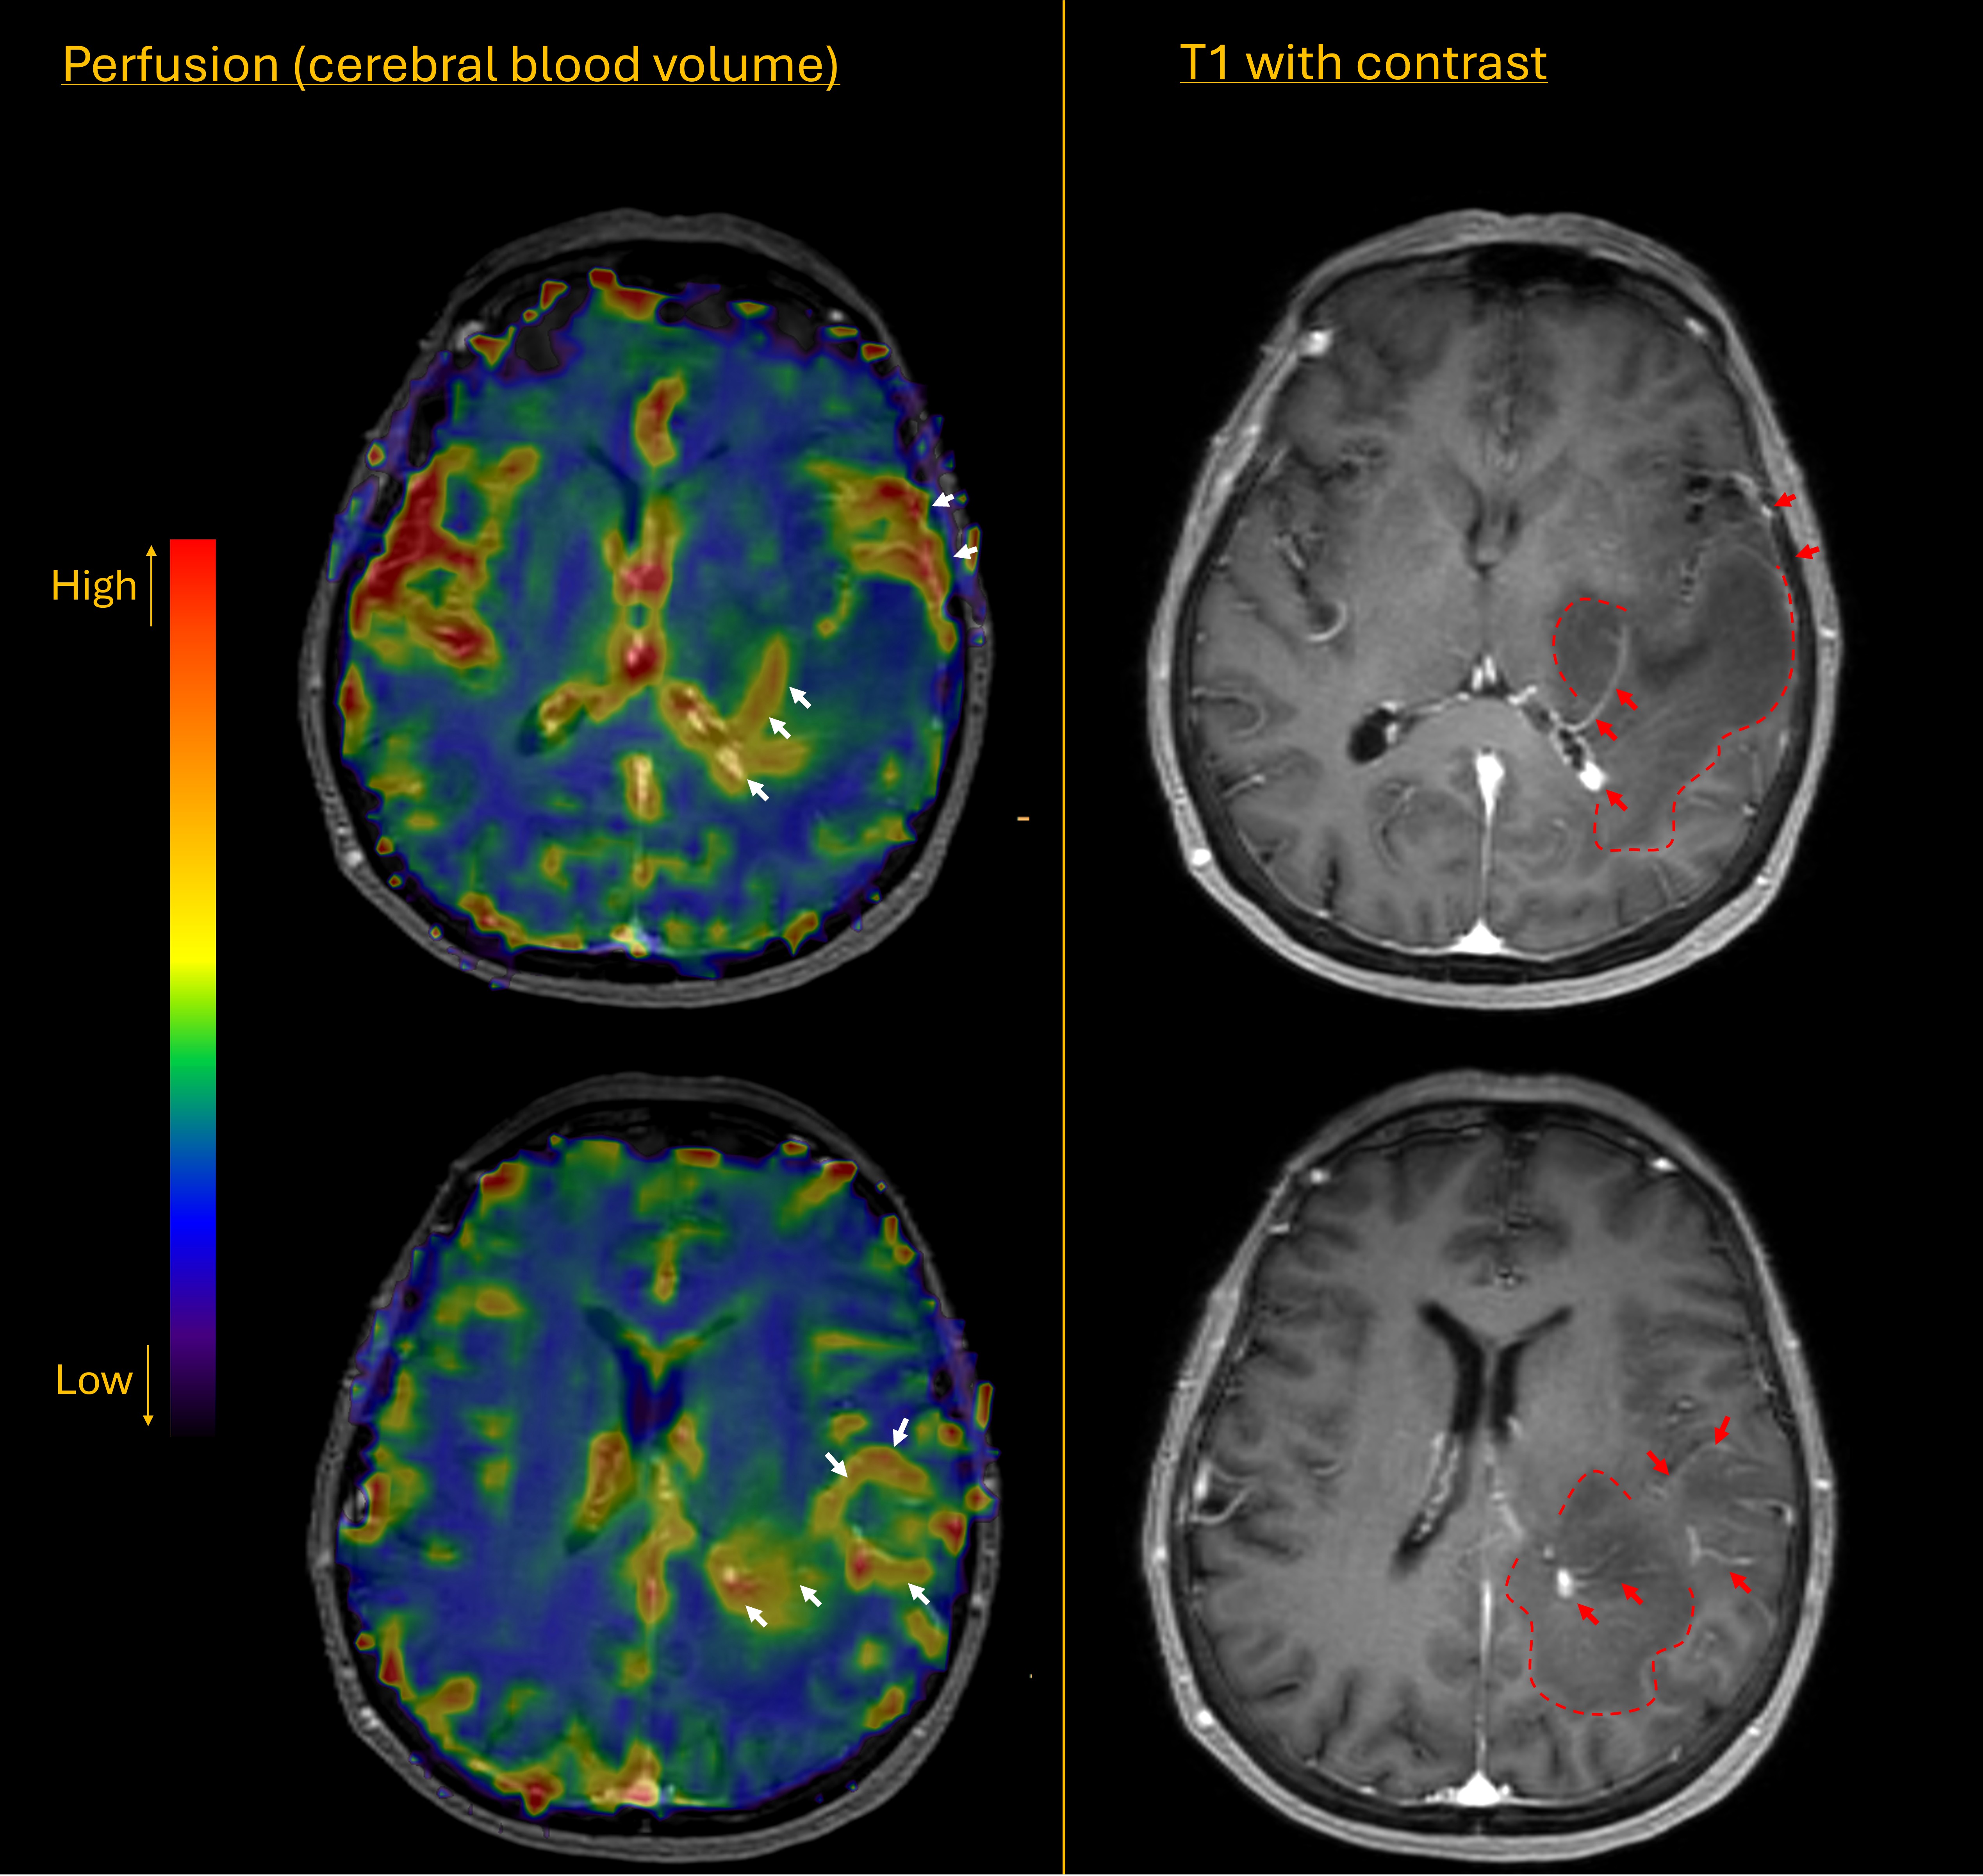

Further imaging was arranged including perfusion studies. Unfortunately these suggested a high grade glioma. There had been a significant increase in tumour size in the short (4 week) interval between scans, and there were now areas of contrast enhancement (red arrows below) surrounding hypointense areas (dashed line) on the T1 images. The perfusion scan showed increased cerebral blood volume in the areas of contrast enhancement (white arrows), suggestive of neovascularity, a marker of high tumour grade.

Perfusion MRI